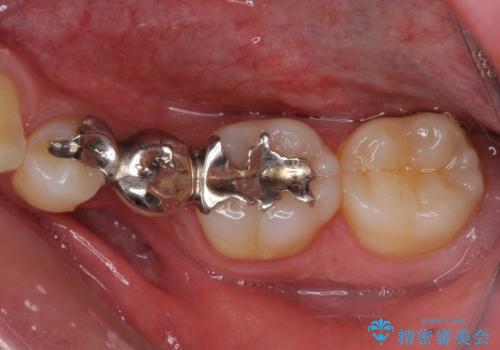

外れてしまった銀歯の詰め物 オールセラミックブリッジにて審美補綴